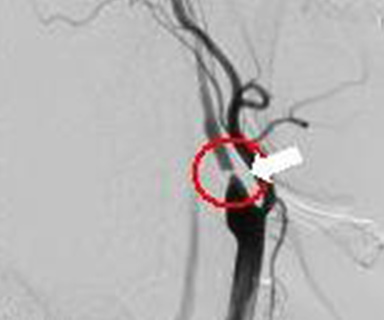

治療後(コイル塞栓術)

プラチナ製コイル

またクモ膜下出血の原因となる脳動脈瘤や動脈や静脈の異常血管(脳動静脈奇形など)をプラチナ製の針金(コイル)を詰め、血流を遮断して治療することができます。

…その他にも、首の動脈が狭くなっていないかを調べたり、狭くなった血管を拡げる治療することができます。

内頚動脈狭窄

治療後(ステント挿入後)